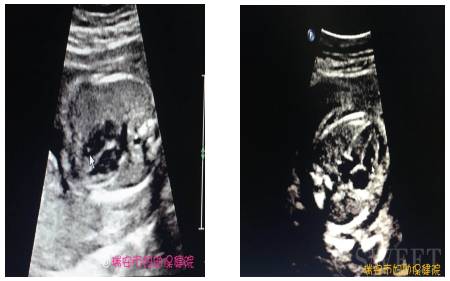

图1:箭头:左心室强光斑 图2:箭头:右心室强光斑

胎儿左(右)心室内强光斑是指超声反射增强的局限性区域,它们会比周围正常的心肌显得更亮一些。在标准的四腔心平扫检查中表现为一侧心室腔的游离区域内心室乳头肌或腱索的点状孤立灶性稍高回声,其回声强度与骨骼相当,并不伴声影,它是一种声像图表现而不是一种心脏畸形,对胎儿心脏的发育及血流动力学无任何影响。